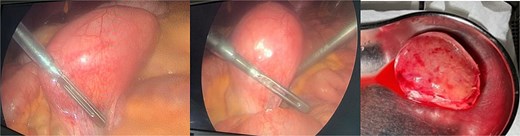

The patient was admitted, and he underwent an emergency laparoscopic appendectomy with partial cecectomy, mesenteric mass excision, and peritoneal lavage. Intra-operative findings included a gangrenous perforated appendix with a right pelvic pus collection, which was aspirated and sent for culture (Fig. 4). A mesenteric mass measuring 6 × 4 cm was noted ⁓70 cm away from the ligament of Treitz distally and excised (Fig. 5). The surgery was completed without complications.

Intra-operative findings included a gangrenous perforated appendix with a right pelvic pus collection.

Intra-operative findings, a mesenteric mass measuring 6 × 4 cm was noted ⁓70 cm away from the ligament of Treitz distally.